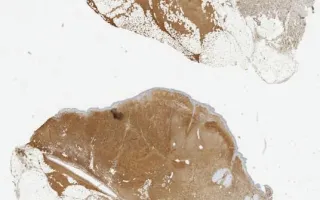

Skin, Dermatofibrosarcoma protuberans, CD34 stain

Microscopically, these tumors have characteristic patterns of a dense proliferation of uniform, bland looking spindle shaped cells arranged in a storiform pattern and also appear in the deep dermis with characteristic "honeycomb-patterned" subcutaneous fat infiltration. It may also show subcutaneous fascia and muscle invasion.

The main differential diagnosis is Cellular fibrous histiocytoma/Cellular dermatofibroma (CDF). Immunohistochemistry shows CD34 is positive in DFSP, whereas Factor Xilia is positive in CDF.

This slide shows CD34 stain. See Related Content for H&E stain.